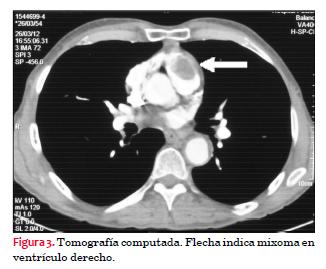

Se realizó angiotomografía de tórax y abdomen, la que informó: masa en VD de 1,5 por 4,3 por 2,5 cm que se extiende hasta TSVD, sin realce significativo. Arterias pulmonares y mediastino normales. No se observan imágenes compatibles con neoplasias extracardíacas (figura 3).